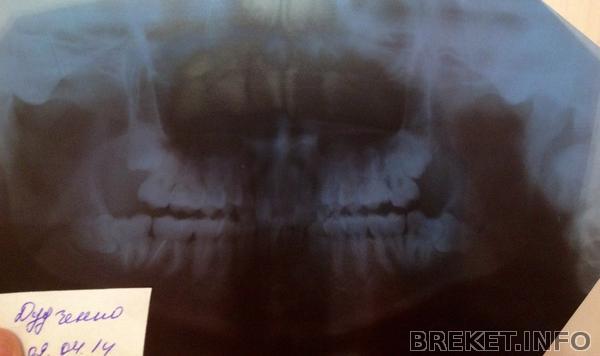

зубки сфотографирую, что бы достать нижнюю 8ку нужно вскрыть слизистую ,причем ее большую часть с вырываемой стороны, это все будет проходить через 7ку, затем нужно выпилить приличный кусок надкостницы , достать эту 8ку не повредив 7ку , ну и потом зашивать, но это все может приобрести обостренный характер...могут быть осложнения..и нервы задеть могут...в общем беда) Спасибо за советы! снимок направлю Андреищеву )

Сочувствую. У вас нижний левый зуб, как у меня верхний правый - растет в 7 так, что надо или сначала 7 удалять потом 8, или разворотить полчелюсти((( Попробуйте обсудить с ортом возможность удаления 5к и стягивания на их место 6 и 7 (в данном случае 8 поспособствуют перемещению этих "тугих" зубов"), тогда и место получите, и 8 может вылезут...

Посмотри на мою восьмерку, она лежала как раз в точно таком же положении, как у тебя (упиралась в 7-ку).

Горизонтальный зуб удалялся конечно посложнее ( можешь подробнее почитать в моем дневнике), но реабилитация, на удивление, проходила легче. 7-ку мне не удаляли и полчелюсти не разворотили))